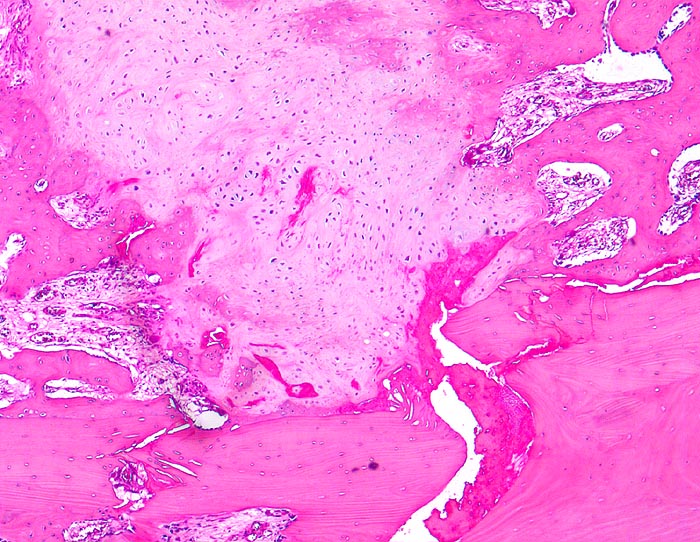

PathoPic – image database / PathoPic ID 4597 - sekundäre Frakturheilung: Frakturspalt

sekundäre Frakturheilung: Frakturspalt

Frakturspalt mit Fibrinablagerungen und neugebildetem, teils mineralisiertem Knorpel. Devitalisierter ortsständiger Knochen mit leeren Osteozytenhöhlen. Markraumfibrose.

Konservativ behandelte Rippenfraktur nach Sturz vor einem Monat.

Der Nachweis von neugebildetem Knorpel entlang der Frakturlinie im Innern des Knochens ist ein Charakteristikum vor allem der Rippenfraktur als Folge einer mangelhaften Ruhigstellung. Die notwendige Resorption des avitalen Knochens führt zu einer Heilungsverzögerung.